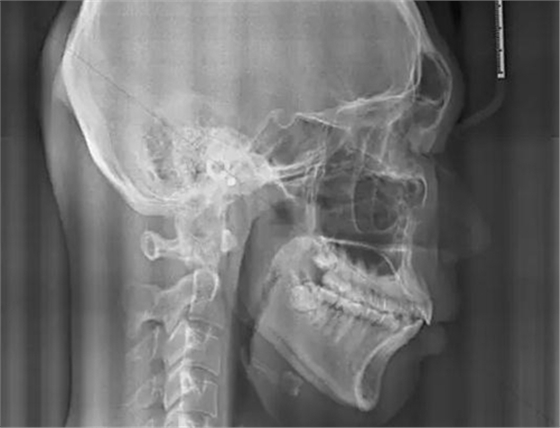

最后我們來對比一下正常的腺樣體和扁桃體的形態(tài)及位置,我們可以看到,正常的腺樣體和扁桃體在同一個位置形態(tài)的差異。